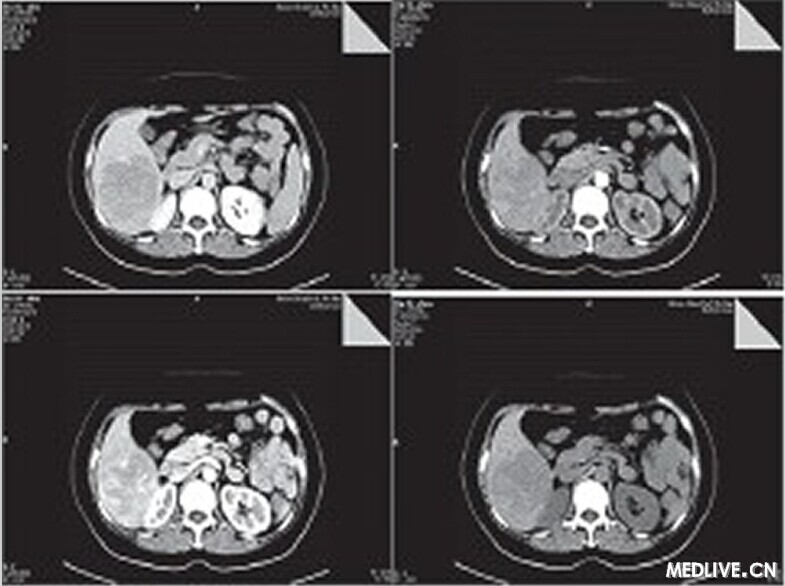

CT檢查平掃示肝右葉見6.6 cm×7.7 cm×8.8 cm塊影,CT值約為49 HU,病變內下緣與右腎上極分界欠清。動態增強掃描動脈期病變內見腫瘤血管影,延遲期呈相對低密度影,三期CT值分別為55.3 HU、85.8 HU、67.5 HU,腹膜后未見腫大淋巴結(如圖1所示)。結論:肝右后葉占位,肝癌可能性大,腹腔積液。

圖1 CT平掃